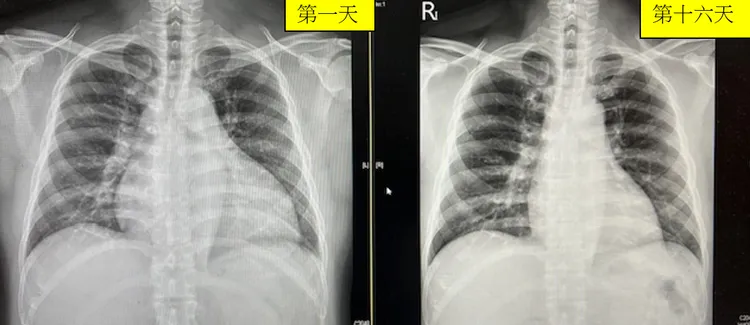

台北市立聯合醫院陽明院區心臟內科主任曾梓維分享,最近半年內就有兩名40至50歲的男性患者,因長期忽視高血壓、高血脂、糖尿病,最終導致心臟衰竭。他們出現嚴重的呼吸困難、無法平躺睡覺、全身水腫等症狀,緊急住院治療。經過藥物控制後,僅16天內心臟大小恢復正常,心臟收縮力(LVEF)也從28%提升至48%,證明現代治療確實能有效改善心臟功能。

病患胸部X光照片。臺北市立聯合醫院陽明院區心臟內科主任曾梓維提供